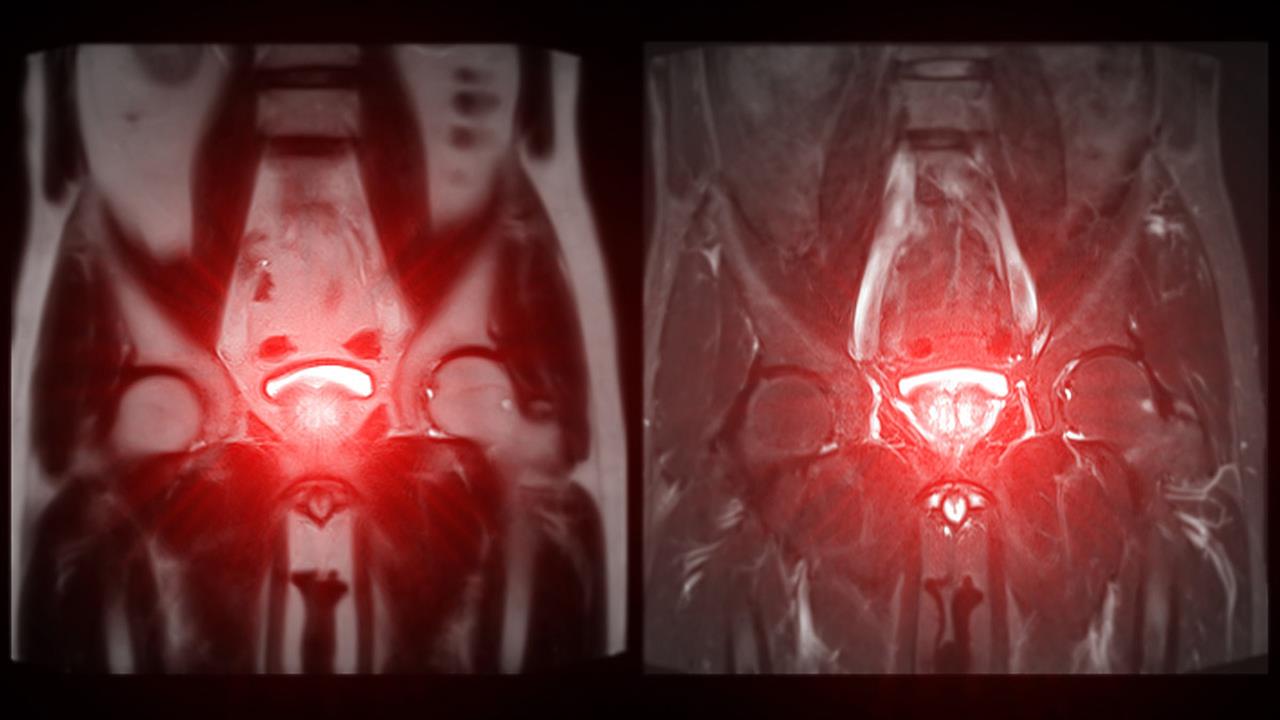

«Σε περίπτωση υποψίας καρκίνου ο ουρολόγος θα συστήσει την πιο ειδική εξέταση για την τοπική διάγνωση που είναι η πολυπαραμετρική μαγνητική τομογραφία (MRI προστάτη). Σε συνδυασμό με τη μαγνητική και ειδικά εφόσον βρεθούν σε αυτήν ύποπτες εστίες, πραγματοποιείται βιοψία προστάτη» εξηγεί ο δρ Νικόλαος Α. Κωστακόπουλος MD, PhD, FEBU Χειρουργός Ουρολόγος-Ανδρολόγος, Εξειδικευμένος στη Ρομποτική Ουρολογία, Επιμελητής A΄ Ουρολογικής Κλινικής Metropolitan General, Διδάκτωρ Πανεπιστημίου Αθηνών ΕΚΠΑ.

Υπάρχει πλέον διαθέσιμο το πιο σύγχρονο σύστημα βιοψίας προστάτη, το Fusion Biopsee, με δυνατότητα σύντηξης της εικόνας της μαγνητικής τομογραφίας και του υπερήχου, για τη λήψη βιοψιών ακόμα και από τις πιο μικρές ύποπτες εστίες, μεγέθους λίγων χιλιοστών.

«Με ειδικό λογισμικό», εξηγεί ο ειδικός, «συνδυάζονται οι εικόνες της πολυπαραμετρικής Μαγνητικής Τομογραφίας που έχει κάνει ο ασθενής, με τον υπέρηχο του προστάτη, ώστε να εντοπιστούν και να χαρτογραφηθούν σε ζωντανό χρόνο, με ακρίβεια χιλιοστού, οι ύποπτες εστίες, από τις οποίες χρειάζεται να ληφθούν βιοψίες. Μαζί με τις ύποπτες εστίες λαμβάνονται και τυχαίες αντιπροσωπευτικές βιοψίες από όλο τον προστάτη, ώστε να επιτευχθεί η σωστή διάγνωση.